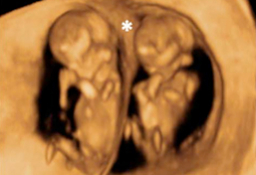

Ecografía de la semana 12

Confirma la edad gestacional y el número de bebés

Los motivos por los que los ginecólogos recomiendan realizar una ecografía en la semana 12 de embarazo tienen que ver con el desarrollo anatómico y el tamaño del feto: ahora es lo bastante grande para comprobar si presenta anomalías. Además, ya se puede ver con claridad si hay uno o dos (o tres) bebés, calcular  la fecha probable de parto teniendo en cuenta la edad gestacional, y confirmar que esta coincide con el desarrollo del bebé. Se puede medir el llamado pliegue nucal (si sobrepasa unos parámetros a veces es indicio de problemas cromosómicos) y, si el bebé se deja, conocer su sexo.